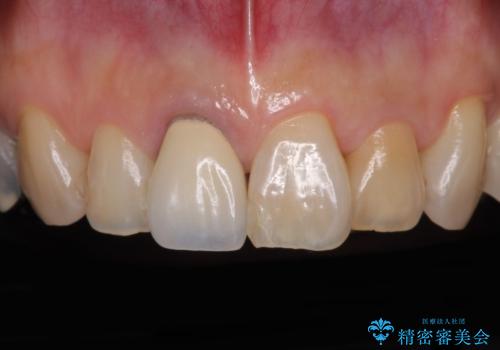

痛む奥歯と見栄えの悪い前歯 オールセラミックによる補綴治療